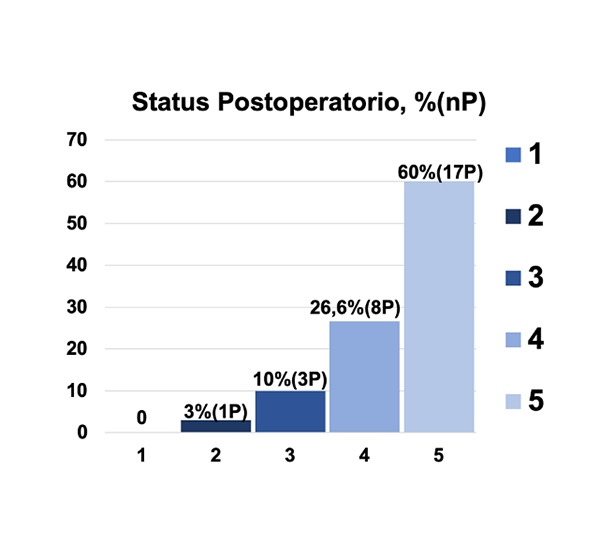

Figura 2. Status Postoperatorio. Se clasificaron los pacientes en cinco grupos distintos en el postoperatorio: (1) - Muerto por otra causa (2) - Clínicamente peor (3) - Clínicamente sin cambios (4) - Clínicamente con mejoría (5). Se presenta el porcentaje de pacientes y número de pacientes por grupos.

De los 30 MRPC tratados durante el periodo de estudio, la edad promedio fue de 52,7 años con un rango de edad de 31-77 años. El sexo predominante fue el femenino con el 83,3%. Al examen físico de ingreso se determinó que el síntoma predominante fue la cefalea en el 53% de los pacientes y los NC mayormente afectados fueron el nervio trigémino en el 67% de las veces, seguido por el complejo VII-VIII en un 40% (Tabla 1). Las zona de implantación más común fue la fisura petroclival en un 66,6% de la veces, seguida por el sector petroso anterior en un 20% de los casos. La zona del clivus mayormente afectada fue el clivus superior en el 81% de los casos y el clivus medio en el 63,3%. El 56,6% de los tumores tuvieron extensión a la fosa media, siendo el 76,6% de gran tamaño. Se observo edema de tronco en el 23,3% de los casos, el cual no estuvo asociado al grado de deterioro neurológico postoperatorio. La arteria basilar se encontraba englobada por la lesión tumoral en el 53,3% de los casos en alguna de sus porciones (Tabla 2). Durante el procedimiento quirúrgico se determinó que el 73,3% de los pacientes intervenidos tenía un buen plano aracnoideo. Casi la totalidad de los tumores no se encontraron calcificados y su consistencia fue intermedia en un 63,3% de los casos. El sangrado fue abundante solo en el 16% de los pacientes. Evaluamos el grado de resección quirúrgica, consiguiendo una resección superior o igual al 95% en el 73% de los casos intervenidos (Tabla 3). En cuanto a la elección de la ruta quirúrgica, el 44% de las veces se eligió un abordaje retrosigmoideo, en un 23 % un abordaje presigmoideo y en un 20% un abordaje transpetroso anterior; fue necesaria la combinación de varios abordajes solo en el 13% de los casos (Figura 1). En el postoperatorio inmediato la mitad de los pacientes tuvo un empeoramiento en la funcionalidad de los NC previamente afectados, con una recuperación en la mayoría de los casos durante los 6 meses posteriores a la cirugía. No existió fistula de líquido cefalorraquídeo en ninguno de los casos (Tabla 4). Se observó recurrencia a dos años de vigilancia en uno de los casos y fue necesario enviar a manejo complementario con radioterapia a dos pacientes. Posterior a una observación neurológica de al menos seis meses, el 86% de los pacientes tenían una mejoría en su calidad de vida o se encontraban igual que previo a la cirugía (Figura 2). Un paciente falleció en el postoperatorio tardío por causa infecciosa. Finalmente presentamos algunos casos ilustrativos (Figura 3) (Figura 4) (Figura 5) (Figura 6) (Figura 7) (Figura 8) (Figura 9)(Figura 10)(Figura 11).

En nuestra serie, se logró realizar una resección total en el 43,3% de los casos; un tercio de estos pacientes sufrieron un déficit neurológico en el postoperatorio inmediato que se resolvió en la gran mayoría de los casos luego de una rehabilitación adecuada. Por otro lado, del 30% de los pacientes a los que se le realizó una resección casi total, la gran mayoría no sufrió un déficit mayor al establecido previo a la intervención. La disponibilidad de radiocirugía se ha asociado con resultados prometedores a largo plazo pero no ayuda a resolver el efecto de masa de lesiones de gran tamaño, donde la única opción posible es la cirugía.11 Luego del análisis hecho de nuestra serie, solo dos de los paciente requirieron manejo coadyuvante con radiocirugía. En la gran mayoría de los casos, no se observó crecimiento posterior a la intervención quirúrgica; esto podría estar en relación con la población femenina que en nuestro caso representó el 83,3% de los pacientes, teniendo en cuenta que se ha mencionado en la literatura por Van Havenbergh12,13 que en esta patología se describe un retraso del crecimiento tumoral luego de la menopausia. La principal indicación de la radioterapia en los MRPC es el tratamiento de residuos o recidivas posterior a una intervención quirúrgica. Sekhar y Schramm recomendaron por primera vez la radioterapia coadyuvante en 198714; desde entonces la controversia se centra en el momento adecuado para indicar esta terapia pudiendo ser temporizada solo en casos en que se observa una recidiva real temprana por RM.15,16